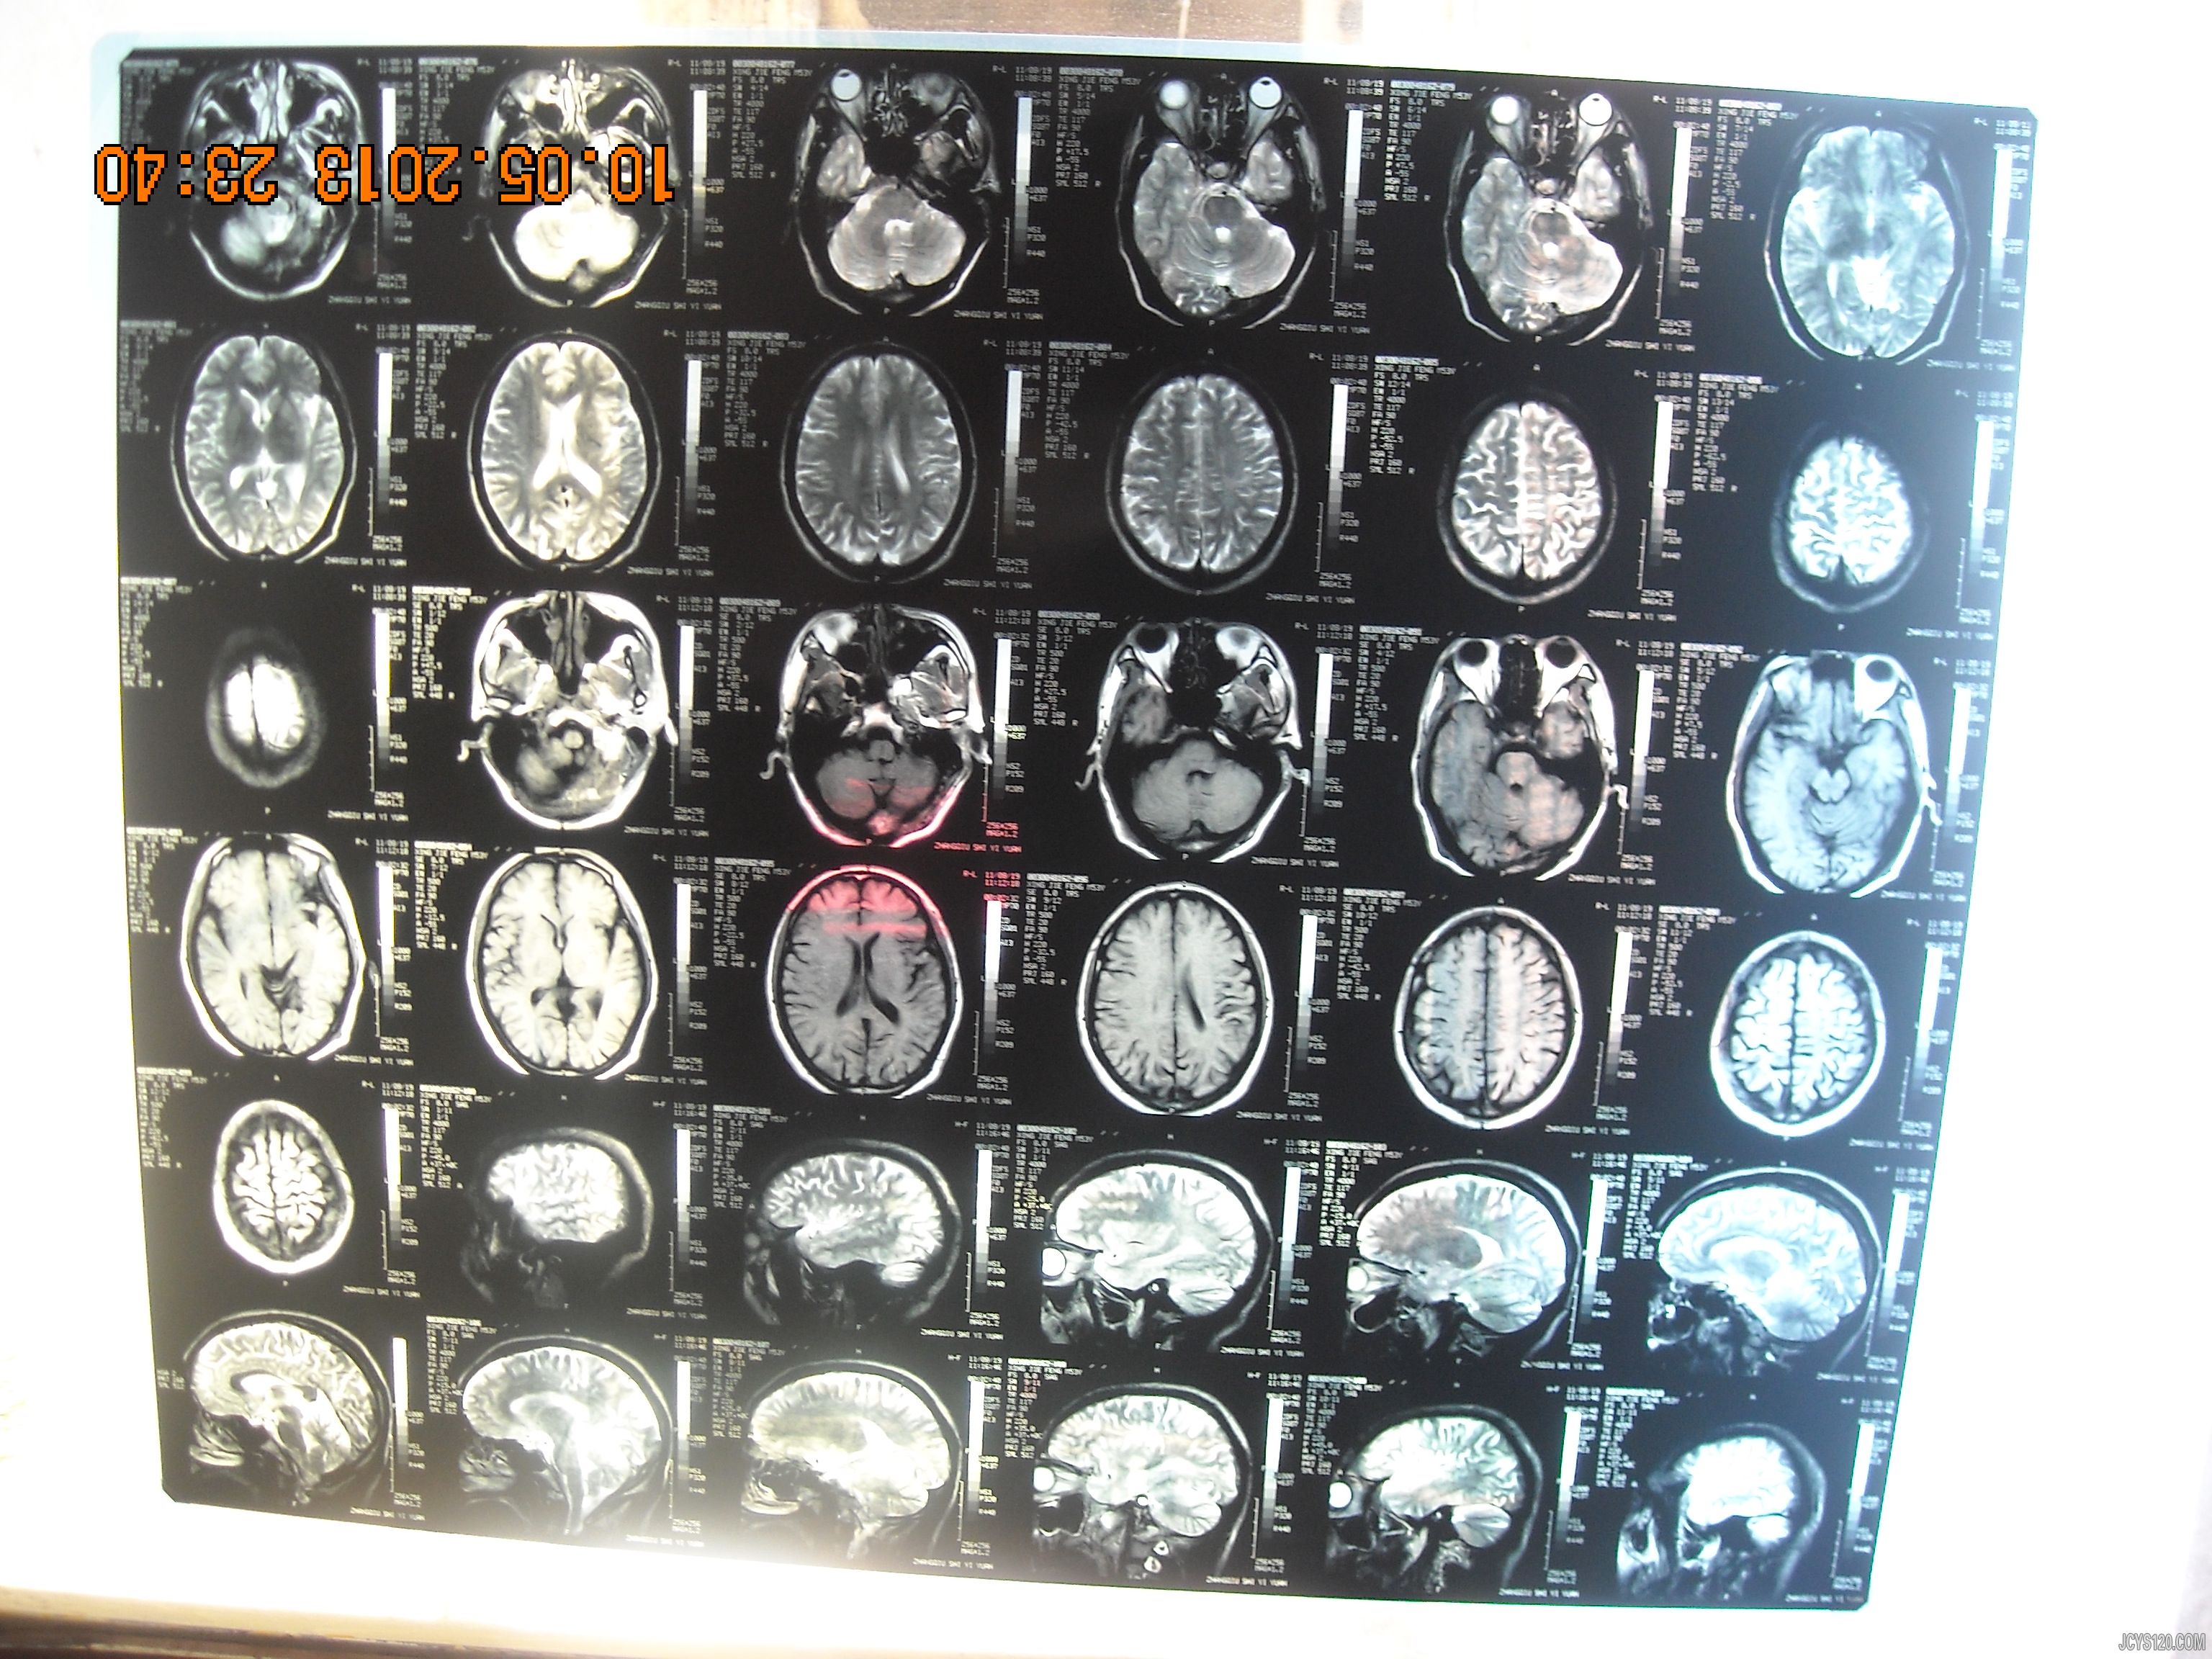

今天有位老师开车接我去给附近村一位大叔看病,但本人难以确诊。敬请各位老师指导 使用全科医师工作站检测,男,53岁,神志清,精神可,查体合作。T:36.3℃ P:70次/min R:17次/min BP:125/80mmHg 右侧肢体活动不灵便,曾在7岁左右有头部外伤史,现查CT无明显外伤痕迹。春秋季发作明显,发作时出现短暂的右侧肢体无力,仅几秒钟,发作时意识清楚。曾在县级医院省立医院做过检查,曾先后诊断TIA,癫痫,服用抗癫痫药物无明显效果,因胃肠道反应停药。